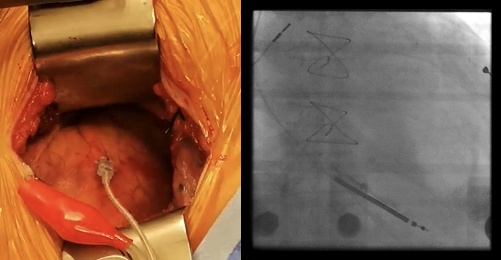

瑞金医院心脏中心是国内较早开展心脏外科手术联合心脏内科介入治疗高危复杂冠心病(也称为“杂交手术”)的中心。杂交手术先由心脏外科在微创小切口行冠状动脉搭桥,随后再由心脏内科分期行介入治疗。

这种联合治疗,体现了以患者为中心的治疗理念。在这种心脏团队治疗模式下,可以大大降低高危复杂冠心病患者的治疗难度,减少手术并发症,提升远期疗效。

1.心脏再同步治疗:由于各种原因无法通过心脏内科介入方法植入左室电极或植入后无反应的患者,通过心外科小切口高选择性左室心外膜最晚激动区域植入电极,帮助优化心内科植入左室电极失败的患者,改善心功能,共同挽救不同原因导致的难治性心力衰竭患者生命,提高了生存率。

心脏内外科杂交优化心衰患者

心脏再同步治疗